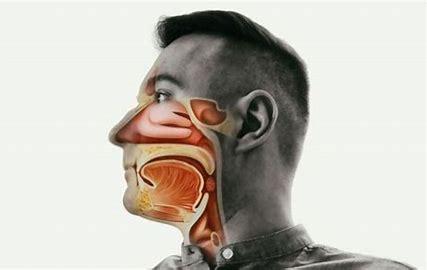

Vous croyez connaître toutes les fonctions du nez ? Cet article vous dévoilera des aspects étonnants, comme la manière dont l'air est filtré ou les effets de l'oxyde nitrique. Découvrez quelques faits surprenants sur la respiration nasale et son rôle dans le bon fonctionnement de votre corps.